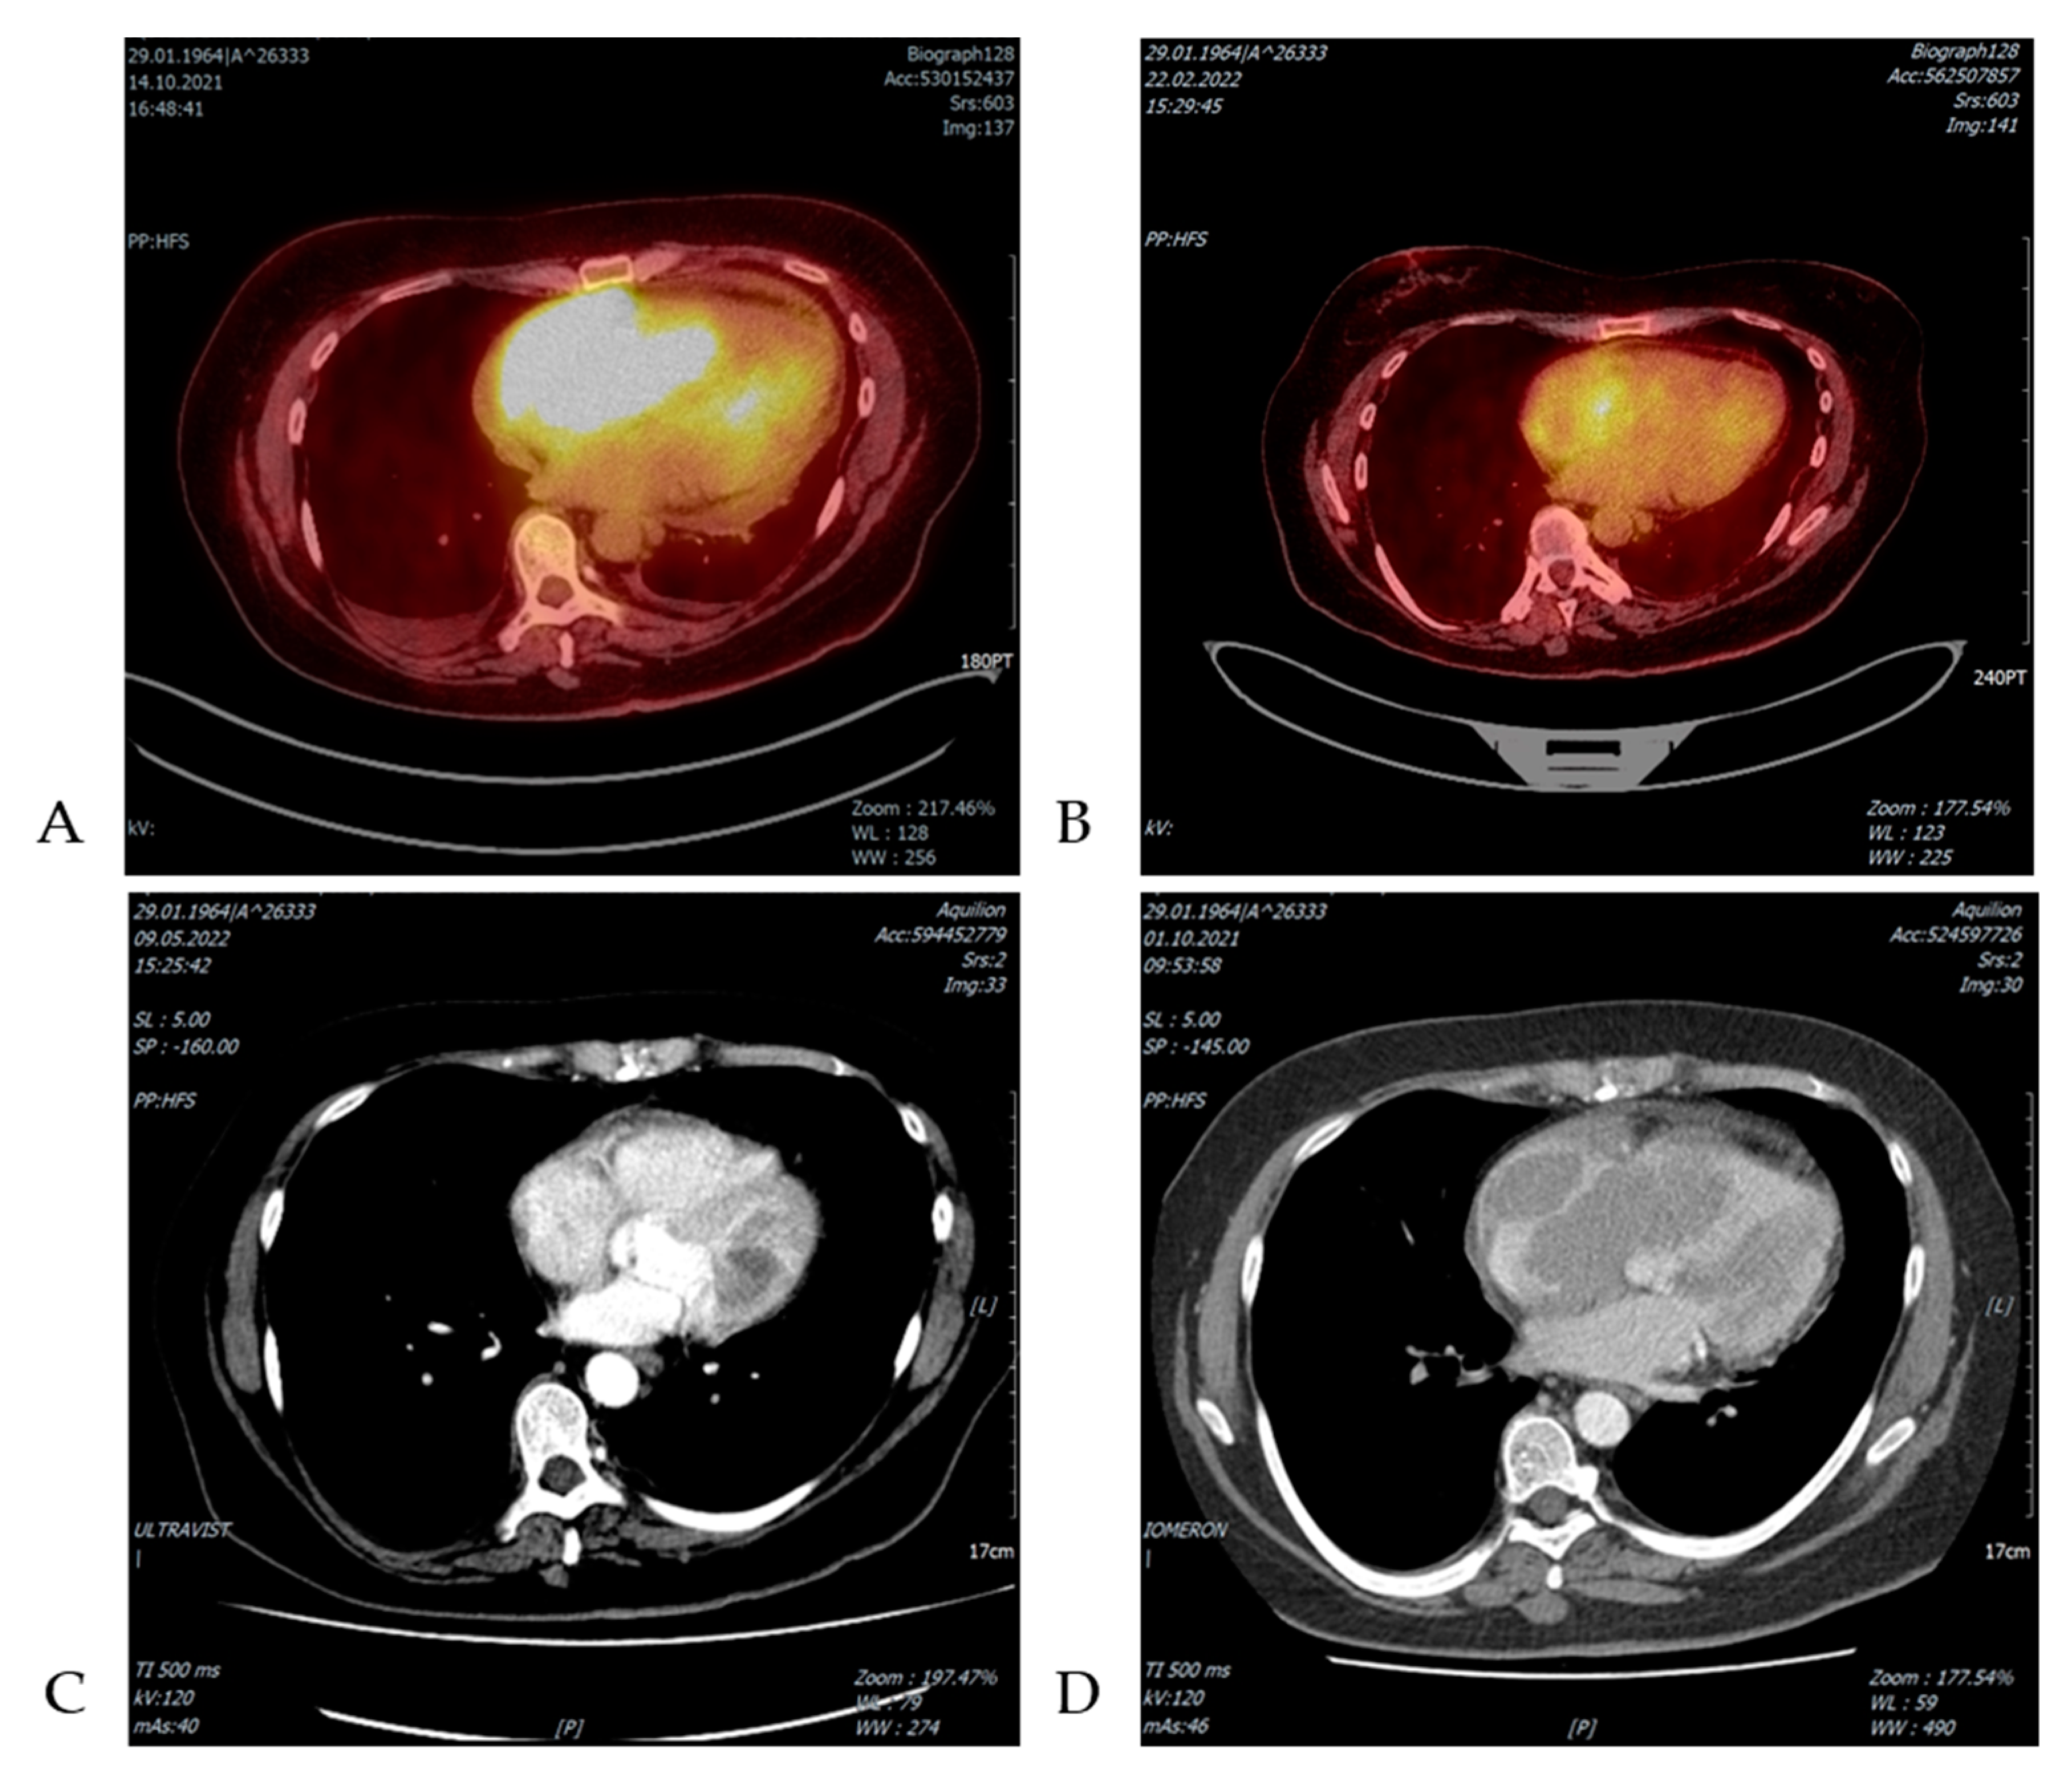

| Zdrenghea et al. 2017 [36] | 61/M | Asymptomatic CLL for 4 years | Cardiac mass (8 × 5-cm) in the right auricle, infiltrating the superior vena cava in CT, in PET-CT) intense FDG uptake of the cardiac mass, large right pleural effusion | 1 cycle of COP and 4 cycles of R-CHOP + ASCT | CR 3 m after ASCT |

| Marra et al. 2021 [37] | 69/W | PB normal, SLL in BM biopsy | Rounded hypodense mass (41 × 58 mm) invaded the right atrium and the interatrial septum revealed by cardiac ultrasound and PET/CT scan | Right atriotomy with tumor mass resection + 6 R-CHOP | Alive and in complete remission at 42 months |

| Pudis et al. 2021 [38] | 75/M | CLL/SLL diagnosed before RT symptoms | Isolated cardiac involvement, PET/CT scan revealed a large cardiac mass in the right atria with high metabolic activity. Biopsy confirmed the diagnosis of DLBCL. | Not reported | Not reported |